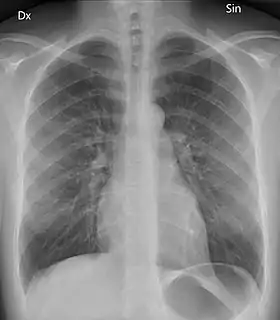

Different views (also known as projections) of the chest can be obtained by changing the relative orientation of the body and the direction of the x-ray beam. The most common views are posteroanterior, anteroposterior, and lateral. In a posteroanterior (PA) view, the x-ray source is positioned so that the x-ray beam enters through the posterior (back) aspect of the chest and exits out of the anterior (front) aspect, where the beam is detected. To obtain this view, the patient stands facing a flat surface behind which is an x-ray detector. A radiation source is positioned behind the patient at a standard distance (most often 6 feet, 1,8m), and the x-ray beam is fired toward the patient.

In anteroposterior (AP) views, the positions of the x-ray source and detector are reversed: the x-ray beam enters through the anterior aspect and exits through the posterior aspect of the chest. AP chest x-rays are harder to read than PA x-rays and are therefore generally reserved for situations where it is difficult for the patient to get an ordinary chest x-ray, such as when the patient is bedridden. In this situation, mobile X-ray equipment is used to obtain a lying down chest x-ray (known as a "supine film"). As a result, most supine films are also AP.

Lateral views of the chest are obtained in a similar fashion as the posteroanterior views, except in the lateral view, the patient stands with both arms raised and the left side of the chest pressed against a flat surface.